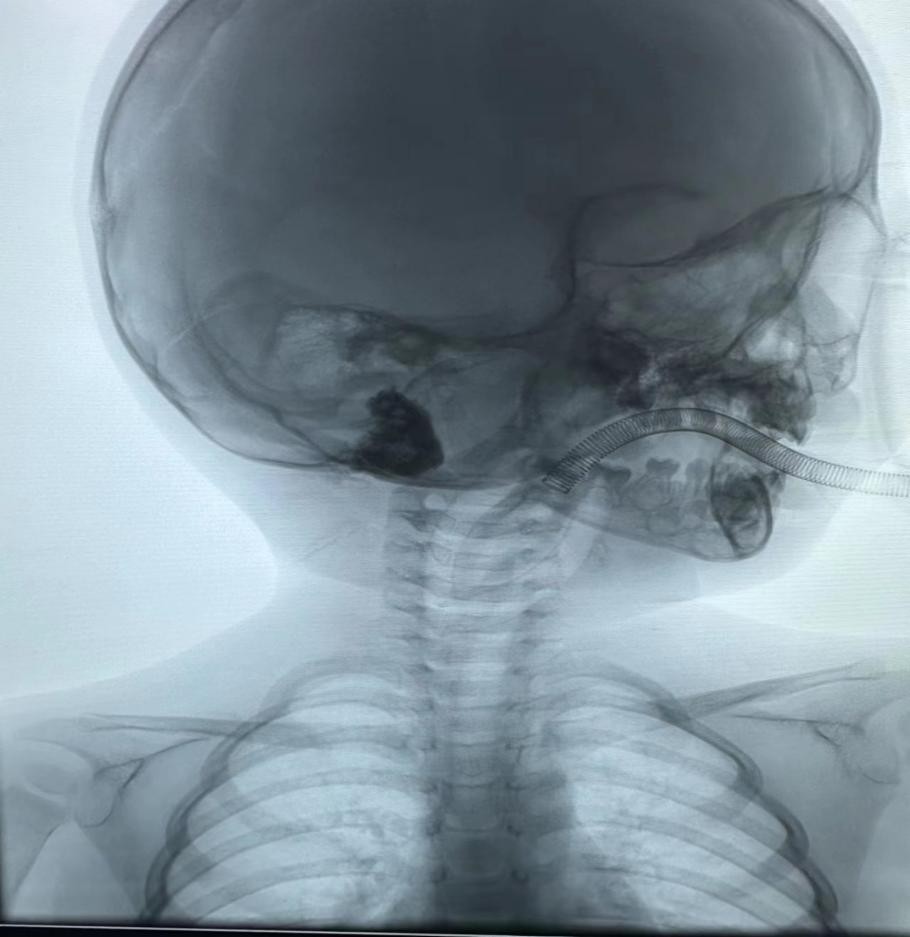

孩子就诊第二天即接受介入硬化治疗。消毒耳后皮肤,在超声及DSA引导下穿刺肿物,成功后用注射器抽出淋巴管液20ml,在DSA透视监视下经皮进行硬化治疗,完成后摄片,显示药液在瘤腔内沉积。手术结束,术中顺利。